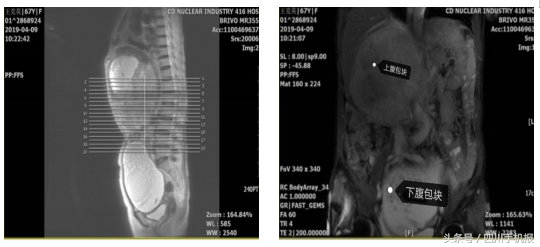

她的上腹右肋下、下腹盆腔内各有一处包块,大小分别约20cm、16cm,最大那个已经十分接近标准足球的大小。

这两个家伙在她的肚子里看似安分,但无时无刻不挤压着她的肠管、肝脏、胰腺、右肾等等器官。

4月19日,手术按计划进行。尽管术前已经用CT、MRI、造影等多种技术,将两个“坏家伙”的模样看了一遍又一遍,但开腹后呈现的景象,还是让医生们皱起了眉头——肿块与周围组织及脏器“亲密无间”,粘连严重。还有横结肠、胆总管、下腔静脉交织出一片迷宫,两处肿块“狡黠地”躲在这些重要“管道”下方,以为医生们会束手无策。